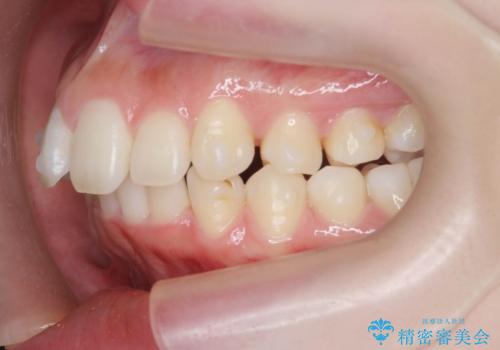

- 高校時代の吹奏楽の部活でサクソフォン(アルト)を担当、「一生懸命練習をしすぎて気づいたら歯並びが悪くなっていた。矯正治療を受けたい!。」

とマウスピース矯正を希望され来院されました。

口腔内の清掃状態の良さに加えて、マウスピースを毎日きっちりと装着し、しっかりと使用していただけたことからワイヤー矯正は行わずにきれいに歯並びを治すことができました。

途中顎位が変わり、マイクロインプラントを併用した上顎臼歯の遠心移動が必要となったため治療が長期化しました。